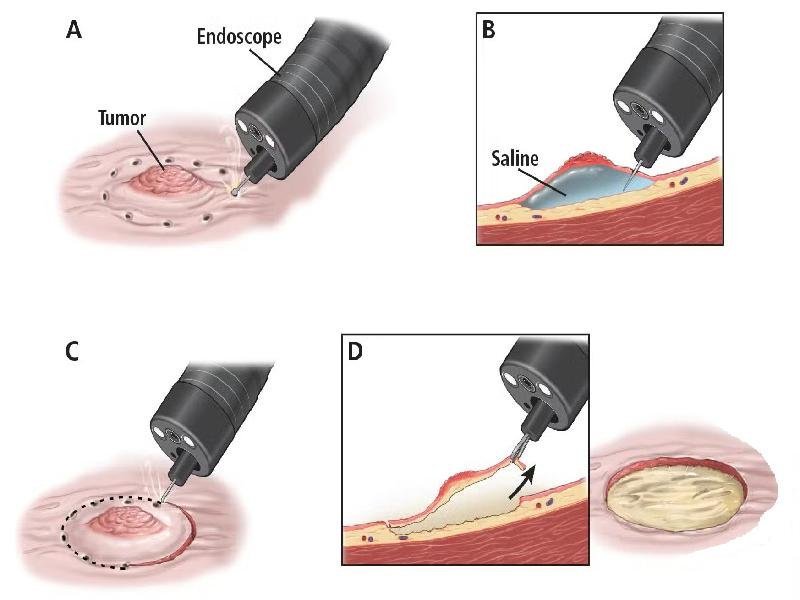

A specialized procedure used to diagnose and treat disorders of the bile ducts and pancreas. Common indications include: